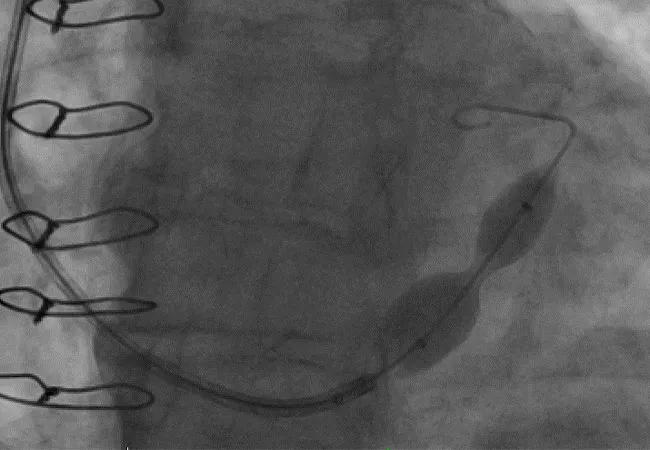

Figure 2. Angiogram of the coronary sinus reducer at baseline (A) and immediately after deployment (B).

The stainless-steel device is implanted percutaneously in the coronary sinus, where it expands into an hourglass shape, leading to local flow disruption with only the narrow central orifice of the device available for blood flow (Figures 1 and 2). The resultant pressure gradient forces blood to flow from the less ischemic epicardium to the more ischemic endocardium, thereby relieving angina.